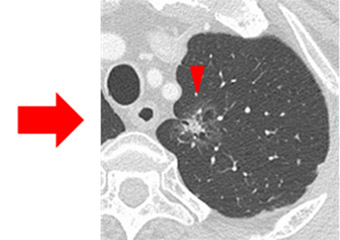

図1:右肺上葉のすりガラス状結節

すりガラス状結節は、「もともと肺に備わっている正常な気管支や血管を覆い隠さない、CT画像における軽度の濃度上昇を伴う領域」と定義されます。図1は右肺上葉のすりガラス状結節の一例です。赤矢印で囲まれたもやっとした淡く白っぽい部分が病変部位になります。病変の内部には血管がすりガラス状結節に影響されずに走行しています。淡いすりガラス状結節は、しばしば胸部単純X線写真では発見することは困難です。